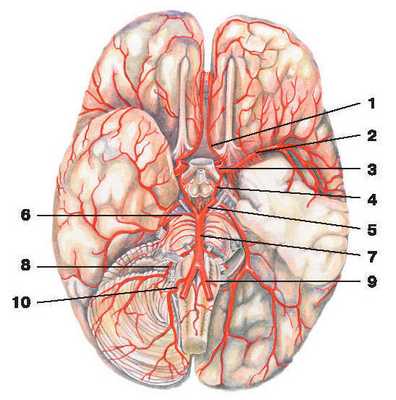

Рис. 217. Артерии мозга:

1 — передняя мозговая артерия; 2 — средняя мозговая артерия; 3 — внутренняя сонная артерия; 4 — задняя соединительная артерия;

5 — задняя мозговая артерия; 6 — верхняя мозжечковая артерия; 7 — основная артерия; 8 — передняя нижняя мозжечковая артерия;

9 — позвоночная артерия; 10 — задняя нижняя мозжечковая артерия

2) передняя мозговая артерия (a. cerebri anterior) (рис. 217) питает кору медиальной поверхности лобной и теменной долей полушарий большого мозга, мозолистое тело, обонятельный тракт и обонятельную луковицу;

3) средняя мозговая артерия (a. cerebri media) (рис. 217) поставляет кровь части лобной, височной и теменной долей полушарий большого мозга;

4) задняя соединительная артерия (a. communicans posterior) (рис. 217) анастомозирует (соединяется) с задней мозговой артерией из системы позвоночной артерии.

Вместе с позвоночными артериями мозговые артерии принимают участие в образовании вокруг турецкого седла кругового анастомоза, называемого артериальным кругом большого мозга (circus arteriosus cerebri), от которого отходят многочисленные ветви, питающие мозг.